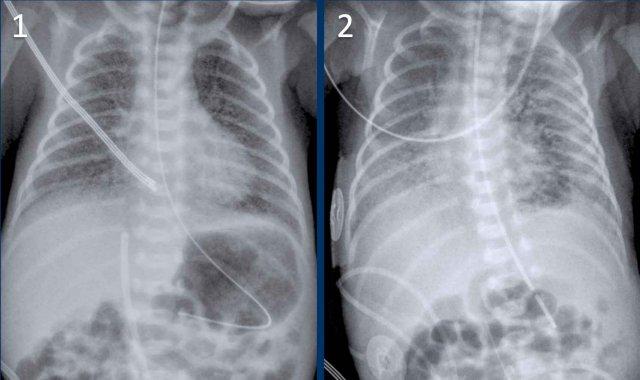

33 tuần + 5 tuần tuổi thai, ngày đầu tiên.

Nhìn vào hình ảnh trước.

Những phát hiện là gì?

Findings:

- Intubated

patient. - Good position of endotracheal tube (ETT). Hyperinflation.

- Symmetric

granular opacifications with air bronchograms. - Definition of heart and vessels

is diminished.

This is a typical case of RDS.

29 tuần + 1, ngày đầu tiên. CPAP.

Nhìn vào hình ảnh lần đầu.

- Reticulogranular opacification

of lungs - Air bronchogram

- Consolidation in the right lower lobe

- Heart, vessels and

diaphragm are poorly defined. - Đặt sai vị trí catheter tĩnh mạch rốn (mũi tên), có thể nằm trong tĩnh mạch phổi.

- Nasogastric tube (NG tube) in good position.

Đây là trường hợp nặng của hội chứng suy hô hấp (RDS).

Chẩn đoán phân biệt bao gồm nhiễm trùng phổi do tình trạng đông đặc không đối xứng.